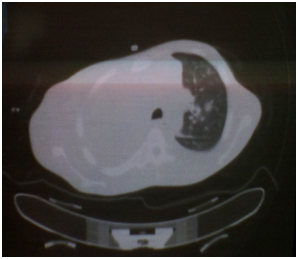

Simple CT scan of skull, thorax and abdomen

Skull: Not encephalic alterations for this study

Lung asymmetry for hipodensity area of lung with tumoral aspect in half or inferior third of the right lung that impresses to obliterate for infiltration the bronchus of the right inferior lobe. This lung mass of lobulated contours and in some espiculated areas, in their inferior end it melts with the mediastinum. They also exist other lung nodules of sub-pleural localization that go from 7 to 15mm, also at pleural level exists thickness of the same one, of nodular aspect, where acquires its biggest thickness right anterobasal ending up measuring 52mm. Slight right pleural effusion, multiple adenophaties in conglomerate in the whole mediastinum from the region infraclavicular. Non alterations in the left lung. Elevation of the right hemidiafragm, not suprarenal lesion, not lesion ocupative of the hepatic space, don't injure of lumbar bone.

This type of malignant tumor is more frequent at level of the parietal pleura, toward inferior portions with a pattern of diffuse growth, it encapsulates the whole lung and it invades thoracic structures; clinically it is presented with pleural effusion recidivist and thoracic pain.11 In our patient the thoracic pain was the initial element that due to the character and the irradiation was interpreted as a somatic etiology. Clinical element that suggest a tumoral diagnosis were the duration and worsened of pain on the time. On physical examination the thoracic expansibility diminished in all right hemithorax and the presence of adenophaties with tumoral consistence in the same side to lend support this etiology (Table 3). In the other hands elements that questioned the diagnosis firstly were the mediastinal participation and the presence of bronchial infiltration (Figure 1) that is usually more frequent in the lymphoma and in the bronchogenic tumor respectively. Besides the patient's age. The quantity of the pleural effusion was always scarce. Imagenological elements to favour was the marked pleural thickness, the nodular pattern of the same one and the left displacement of the mediastinum (Figure 2). Humoral element that support the diagnosis were the anemia, thrombocytosis and decreased iron level (Table 4) characteristic of this type of process. Although a marker unique immunohistochemistry doesn't exist with the enough specificity to carry out the diagnosis of malignant mesothelioma, the common thing is to use a panel of markers. It should be considered that the pancitoqueratinas tints to most of the mesothelioma. For mesothelioma epithelioid the positive markers include the calretinina, Citoqueratinas (CK) 5/6, the nuclear Wilms tumor Antigen type 1 (WT-1) and the podoplanina (D2-40). For the adenocarcinoma are used the carcinoembrionary antigen, Ber-EP4, TTF-1 and napsina A,12 which confirmed the definitively diagnosis in this patient. In relation to the treatment, the radiotherapy and the chemotherapy have shown little influence on the survival are high the mortality and the surgical morbidity (near at the five and 50%, respectively). The main objective of this it consists on palliating the main symptoms, the dysnea and the thoracic pain, it can include chemotherapy, radiotherapy and the surgical intervention (or both).13 In this case we decided to begin treatment with Carboplatino 350 mg/m2/day, Paclitaxel 175 mg/m2/day and Vinblastina 6 mg/m2/day all regimens each 21 days. Because the combination of several chemotherapy including a Platino compound may result more effective than the monotherapy,14, 15 being able to improve partially the symptomatology.

Figure 2 Simple CT Scan that show left mediastinal displacement.